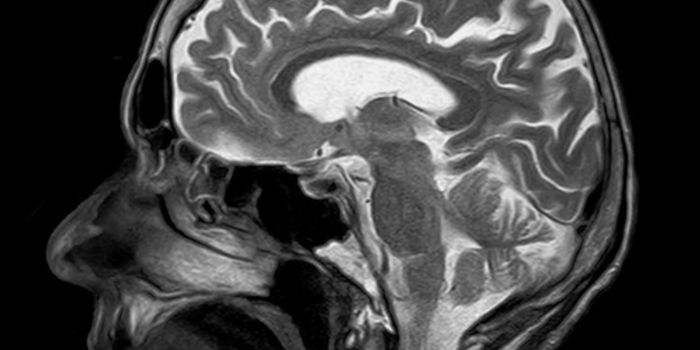

Read the latest articles about newly released neuroscience research and advances in experimental techniques. Topics include research news in neuroscience, neurology, psychology, brain science and cognitive sciences.